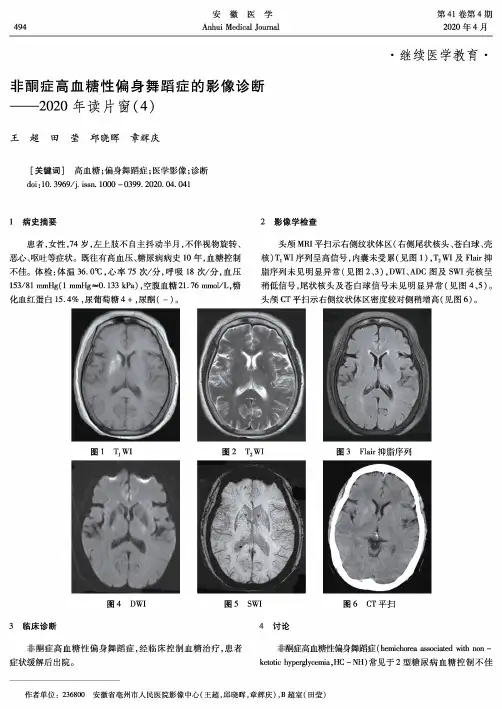

第41卷第4期2020年4月安徽医学Anhui Medical Journal494•继续医学教育•非酮症高血糖性偏身舞蹈症的影像诊断——2020年读片窗(4)王超田莹邱晓晖章辉庆[关键词]高血糖;偏身舞蹈症;医学影像;诊断doi :10. 3969/j. issn. 1000 - 0399. 2020. 04. 0411病史摘要2影像学检查患者,女性,74岁,左上肢不自主抖动半月,不伴视物旋转、 头颅MRI 平扫示右侧纹状体区(右侧尾状核头、苍白球、壳恶心、呕吐等症状。

既往有高血压、糖尿病病史10年,血糖控制 不佳。

体检:体温36. 0^ ,心率75次/分,呼吸18次/分,血压核)T\WI 序列呈高信号,内囊未受累(见图1) ,T 2WI 及Flair 抑脂序列未见明显异常(见图2、3) ,DWI 、ADC 图及SWI 壳核呈153/81 mmHg( 1 mmHg~0.133 kPa),空腹血糖21.76 mmol/L,糖稍低信号,尾状核头及苍白球信号未见明显异常(见图4、5)。

化血红蛋白15.4%,尿葡萄糖4 + ,尿酮(-)。

头颅CT 平扫示右侧纹状体区密度较对侧稍增高(见图6)。

图1 T]WI 图2 T 2WI 图3 Flair 抑脂序列图4 DWI图5 SWI图6 CT 平扫3临床诊断4讨论非酮症高血糖性偏身舞蹈症,经临床控制血糖治疗,患者 非酮症高血糖性偏身舞蹈症(hemichorea associated with non -症状缓解后出院。